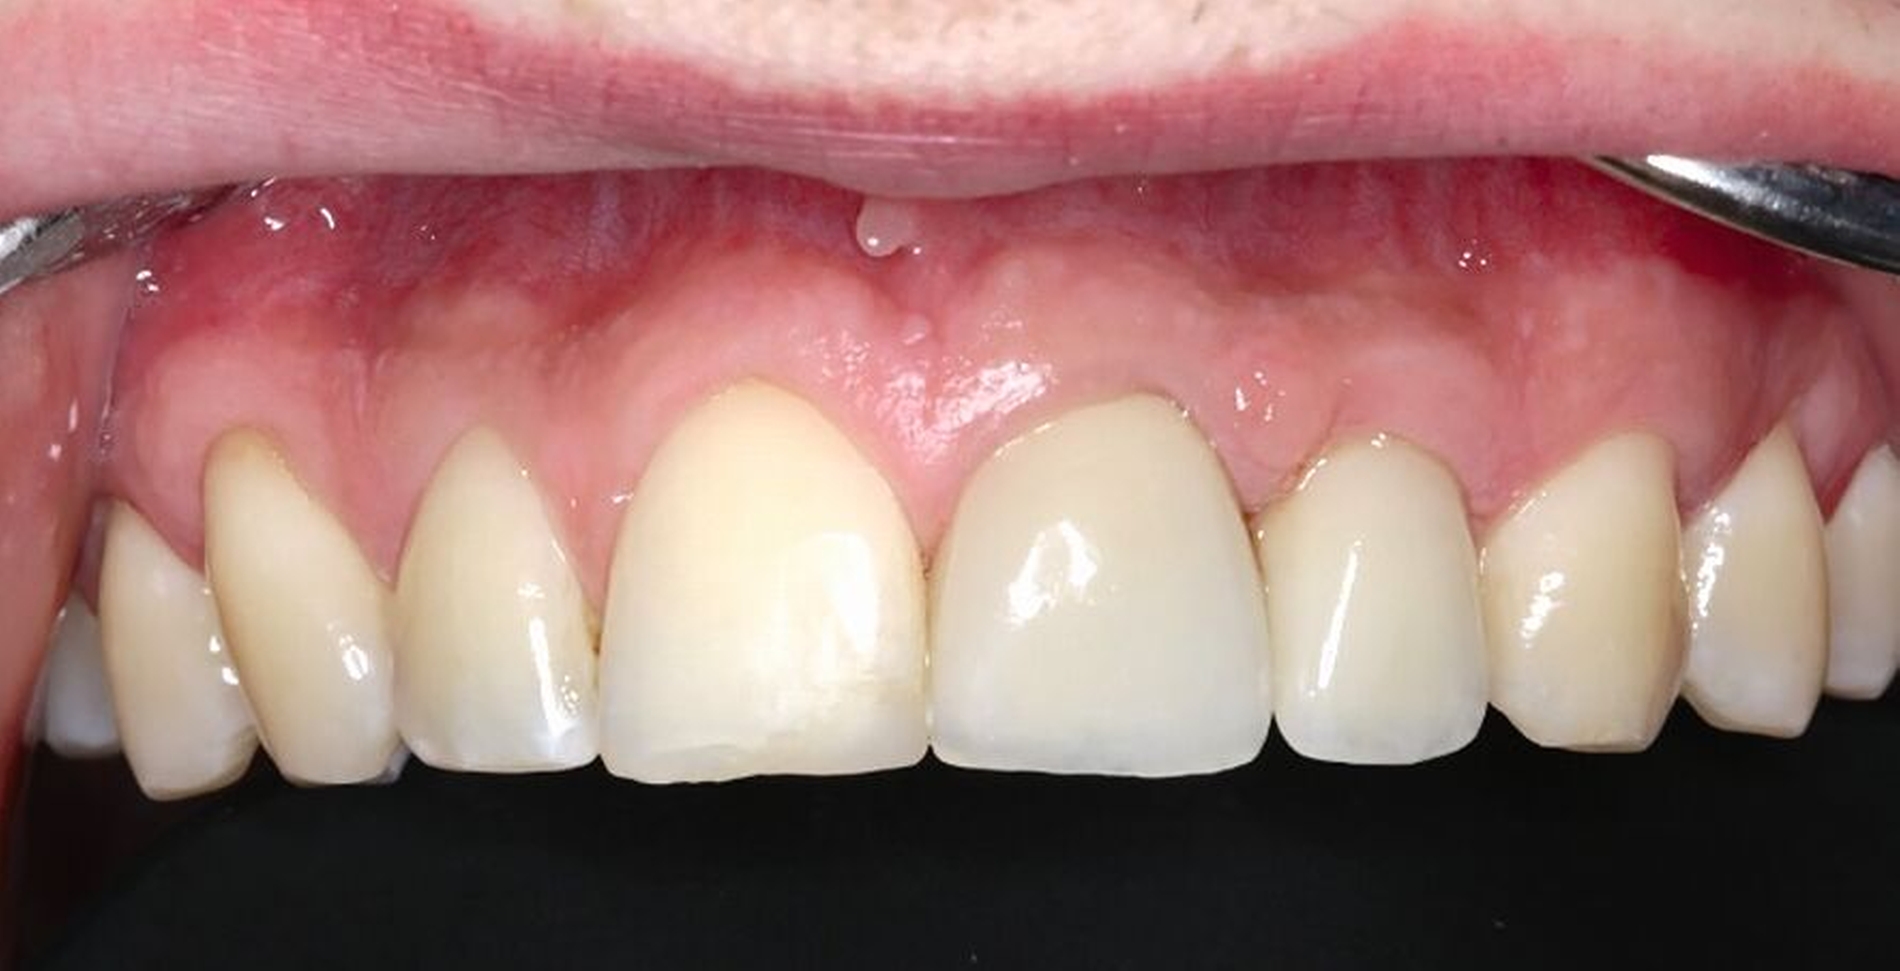

Als die Wurzel des Zahnes 22 ausreichend extrudiert war, wurde ein adhäsiver Stift-Stumpf-Aufbau inseriert (Abbildungen 24 und 25). Die Krone an Zahn 21 wurde entfernt, da diese durch das Trauma inzisal beschädigt worden war und der Patient eine Neuanfertigung wünschte.

So konnten beide Lithiumdisilikat-Keramikkronen im Labor verblockt hergestellt werden, um einer unerwünschten Re-Intrusion vorzubeugen. Abbildung 26 zeigt die Situation zur Aufnahme der prothetischen Versorgung. In Abbildung 27 ist die Situation nach Einsetzen mit adhäsivem Befestigungskomposit zu sehen. Bei der Kontrolle ein Jahr nach Einsetzen der Versorgung zeigt sich klinisch der Therapieerfolg (Abbildung 28).